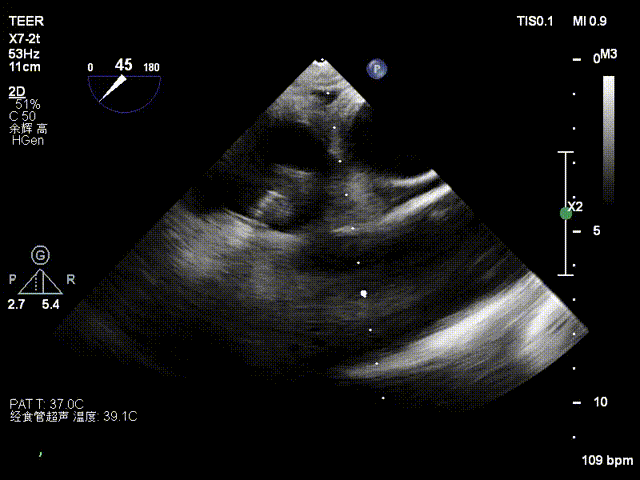

患者为56岁男性,因5天前反复出现活动后胸口隐痛感,持续数分钟到数小时不等,超声心动图提示:1.二尖瓣后瓣脱垂并重度关闭不全;2.左心大;3.三尖瓣反流;4.左心收缩功能正常。

经食道超声检查提示:二尖瓣瓣叶增厚冗长2区后瓣脱垂呈连枷样改变,考虑Barlow’s综合征。评估解剖结构:前叶长度:3.3cm,后叶长度:2.8cm,脱垂宽度:26mm,脱垂高度:19mm,瓣口面积:7.5cm²。

术前影像

3D

X-plane 1区

X-plane 2区

X-plane 2区彩色